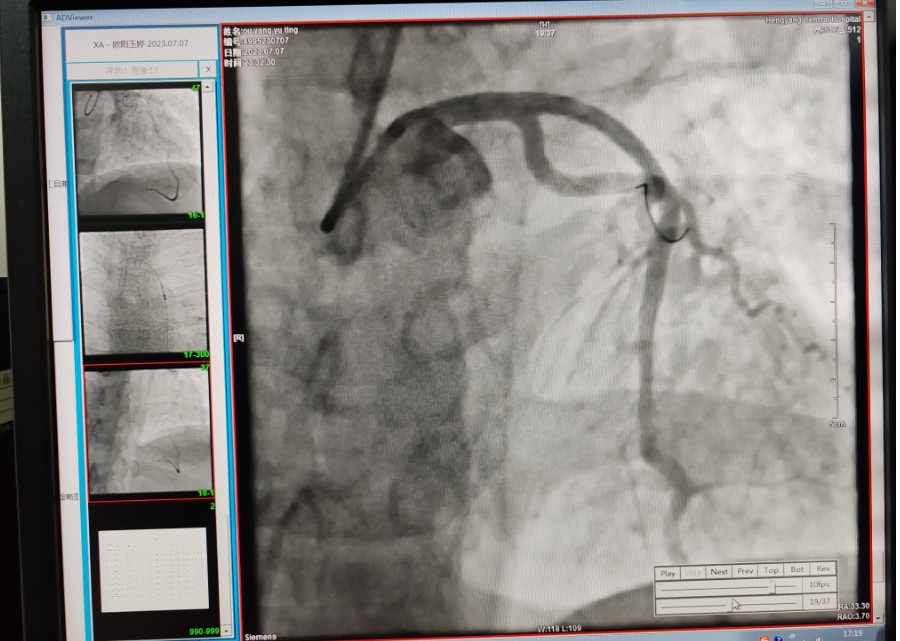

22:29分患者經(jīng)院內(nèi)綠色通道送達(dá)導(dǎo)管室,手術(shù)由雷剛副主任醫(yī)師主刀,楊繼賀副主任醫(yī)師為第一助手,介入技師及護士密切配合,聞訊而來的趙慶禧主任醫(yī)師坐鎮(zhèn)協(xié)調(diào)指揮。22:37分手術(shù)開始,冠脈造影顯示心臟上最重要的一條冠狀動脈-前降支開口齊頭閉塞,血管粗大且血栓高負(fù)荷,非??简灲槿胄g(shù)者的手術(shù)能力,一旦發(fā)生冠脈無復(fù)流或操作不慎血栓帶入回旋支導(dǎo)致循環(huán)崩潰,病人幾乎無生還希望;此時,患者手術(shù)臺上仍持續(xù)胸痛,且血氧飽和度在高流量吸氧狀態(tài)下不到80%,雷剛副主任醫(yī)師一方面指揮鎮(zhèn)靜鎮(zhèn)痛及抗心衰治療,一方面緊急啟用IABP(主動脈球囊反搏),然后精細(xì)操控細(xì)如發(fā)絲的介入導(dǎo)絲迅速通過病變,并予冠脈球囊擴張、冠脈內(nèi)溶栓、抗痙攣藥物使用、植入冠脈支架,最終成功開通“罪犯”血管,且無手術(shù)并發(fā)癥發(fā)生,整個過程張弛有度、快慢結(jié)合、一氣呵成?;颊咝g(shù)后胸痛明顯好轉(zhuǎn),血氧飽和度上升至96%,術(shù)后1天轉(zhuǎn)出監(jiān)護病房,第3天拔出IABP,目前已康復(fù)出院。